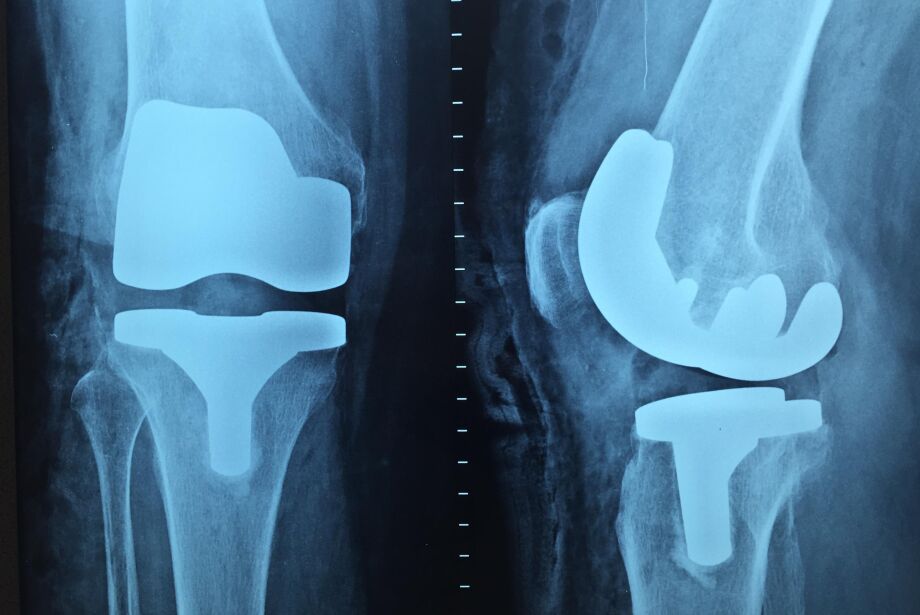

O joelho é uma das articulações mais complexas do organismo, justamente por envolver um osso (patela), superfícies ósseas de outros 2 ossos (fêmur e tíbia) e uma série de ligamentos, como o ligamento cruzado anterior e os meniscos.

No joelho também há os meniscos (2, um mais interno, medial e outro mais externo, lateral), que funcionam como amortecedor, evitando que a cartilagem da articulação sofra todo o impacto.